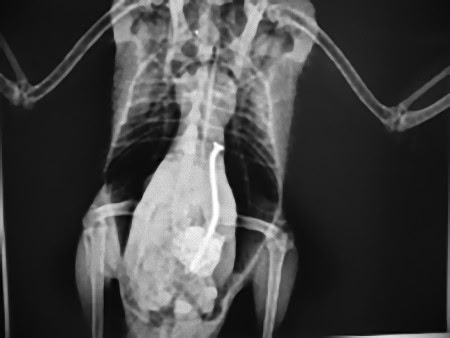

この画像を大きなサイズで見る1歳のダックスフンド、2インチのミシン針

この画像を大きなサイズで見る